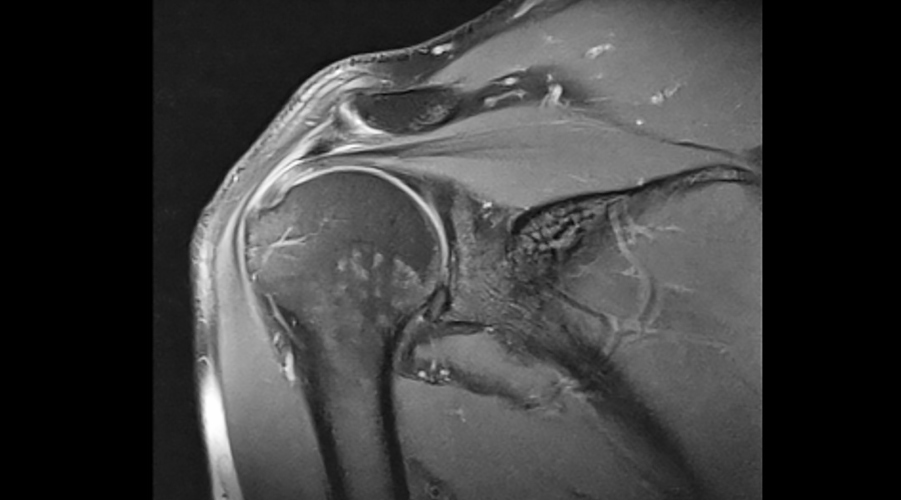

Magnetic Resonance (MRI)

MRI is a highly sensitive and specific method in the identification and evaluation of soft tissues such as the Rotator Cuff, soft tissue problems, bone marrow edema and tears.